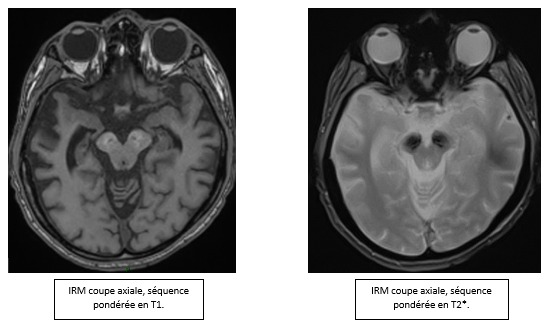

- Comment analyser-vous l'IRM ?

- L’ IRM cérébrale, à gauche en séquence T2 sagittale montre une atrophie vermienne. À droite, en séquence FLAIR axiale elle montre un hypersignal non significatif de substance blanche.